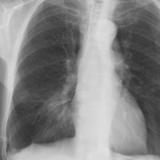

Case 1 PA